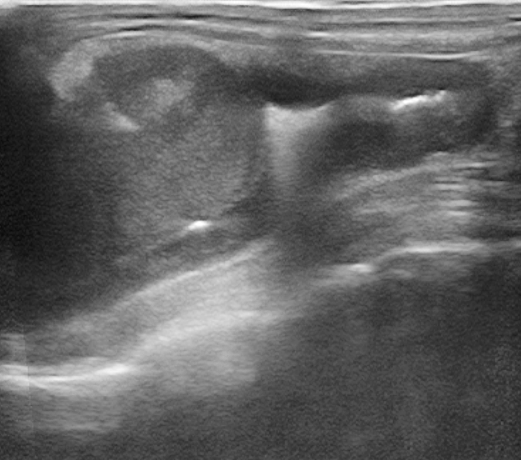

EVOLUÇÃO: INDICAÇÃO DE EXAME ULTRASSONOGRÁFICO

- Foi realizado exame ultrassonográfico abdominal que revelou presença de discreta quantidade de líquido livre em cavidade abdominal, linfonodos esplênico e mesentéricos acentuadamente aumentados e de ecotextura heterogênea. Visibilizou-se uma estrutura parenquimatosa aderida a um segmento de alça intestinal jejunal, homogênea, de formato ovalado, medindo 2,14cm x 1,44cm, vascularizada ao Doppler colorido e que invadia e obstruía parcialmente o lúmen intestinal, sugerindo processo neoplásico.

Doppler estrutura 1º exame